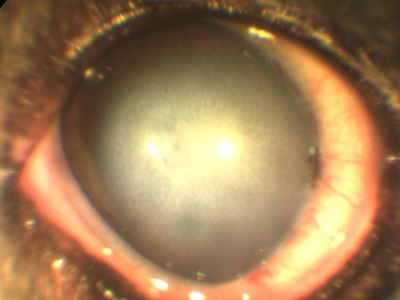

creșterea presiunii intraoculare (glaucom) va acționa, de asemenea, asupra celulelor endoteliale prin deteriorarea acestora.

coroida Inflamația (uveita) dă turbiditatea umidității în camera anterioară a vasului poate sângera de fibrina, lipide (în încălcarea metabolismului grăsimilor).

Infecțiile „Hyperimmunisation“ viermi intestinali, tulburări metabolice pot provoca inflamații (uveită).